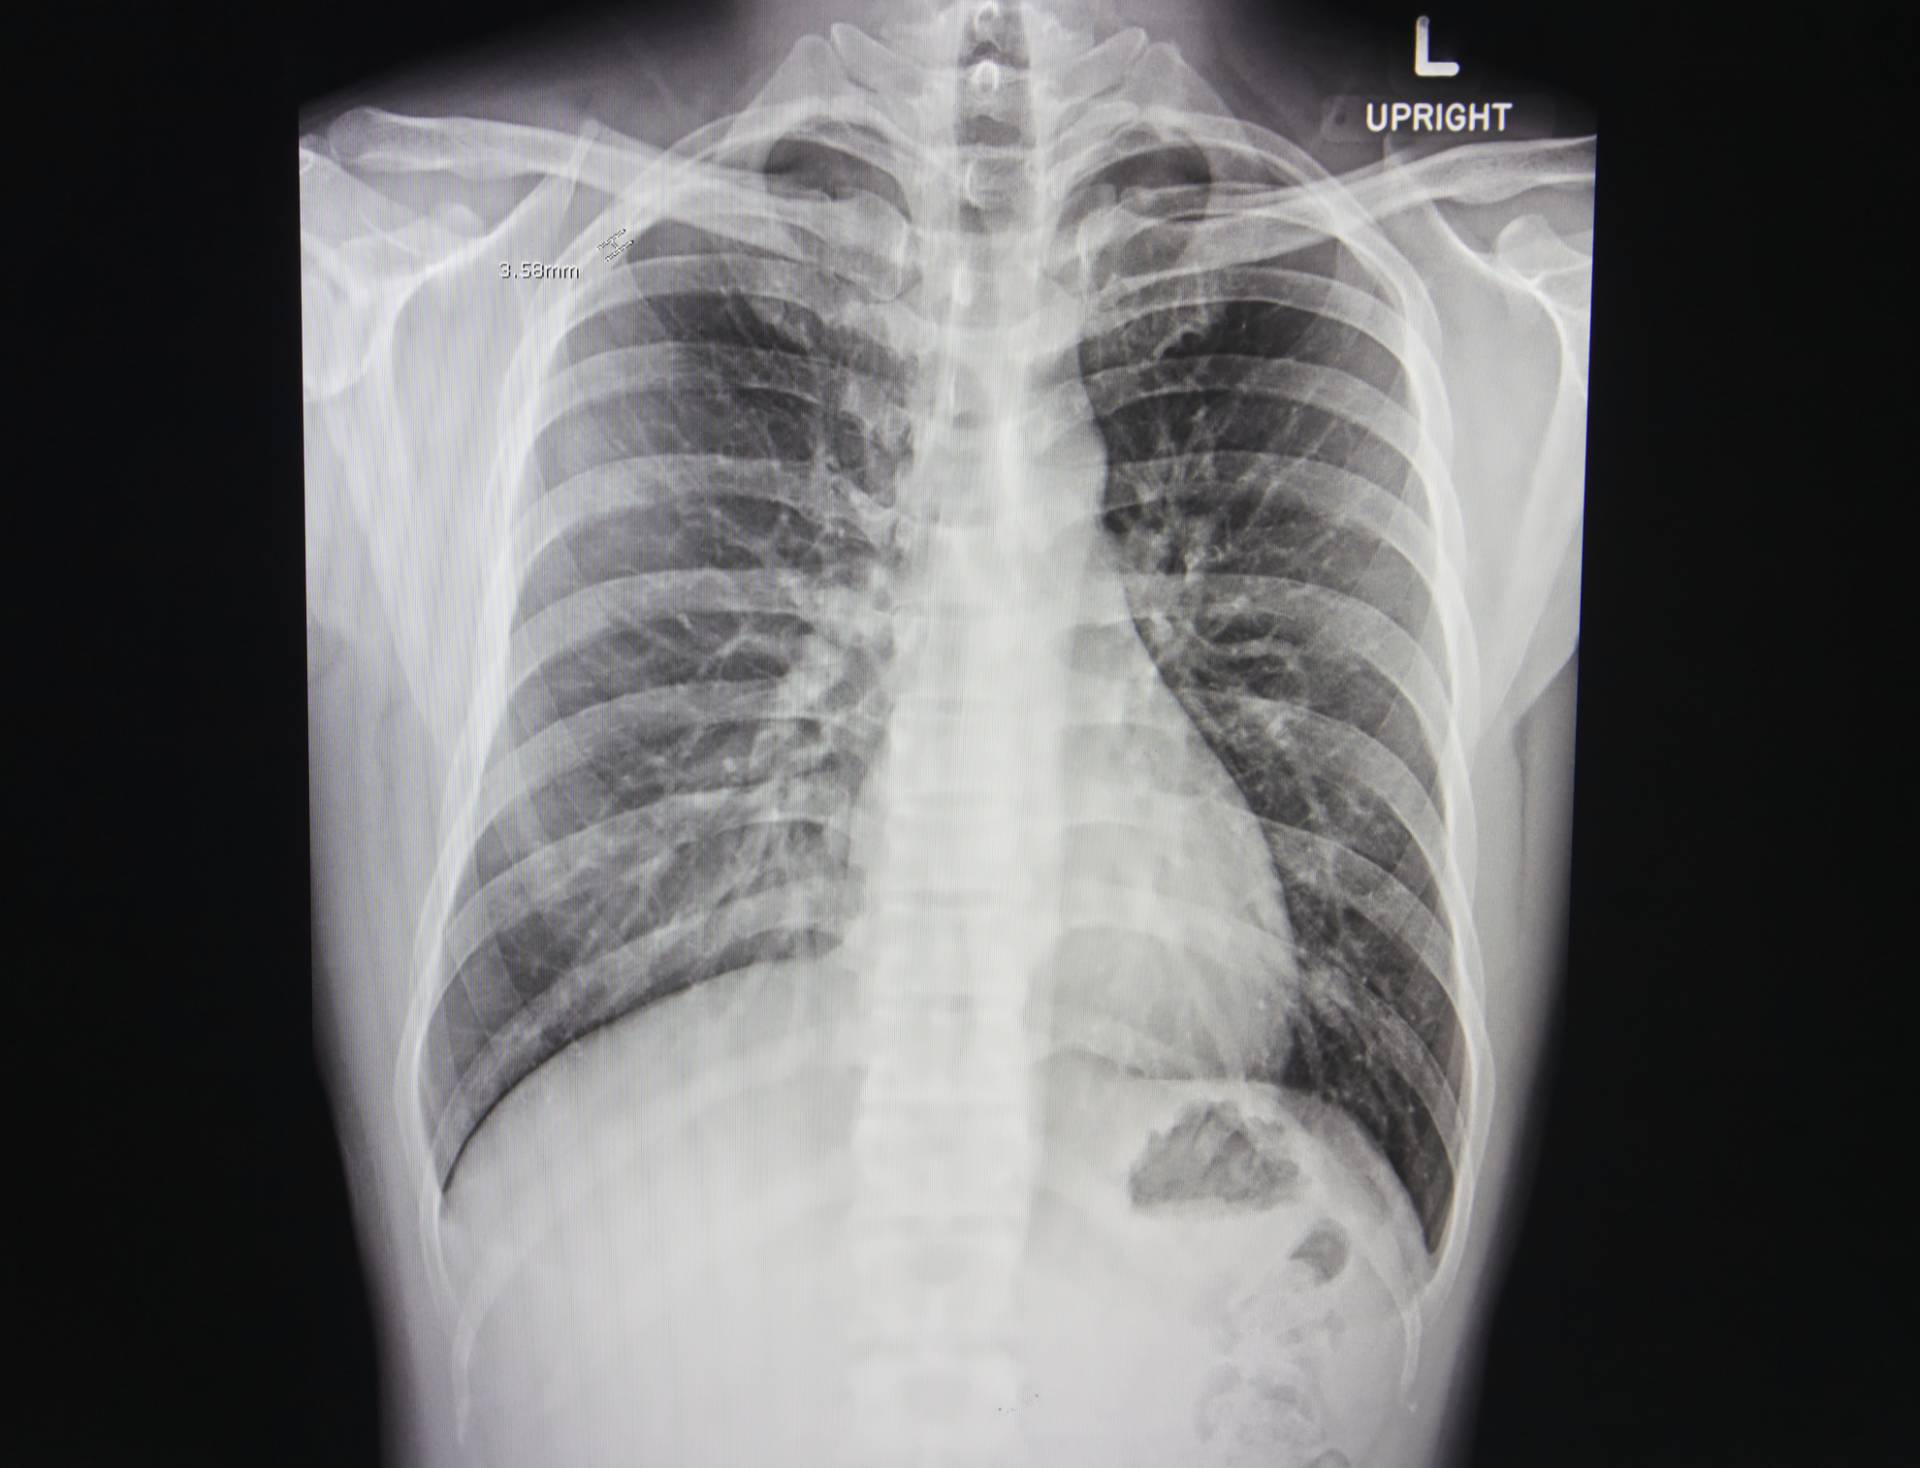

Lung cancer is the biggest cause of cancer deaths in the UK. 5-year survival rate is poor at just 14.6% and 30% of patients die within 90 days of diagnosis, with around 48,600 new cases and 35,300 deaths annually. The National Optimal Lung cancer Pathway (NOLCP) recommends rapid progression from chest X-ray (CXR) to computerised tomography (CT) scan to reduce time to diagnosis for Lung cancer patients. However, radiology capacity and increasing workload hinders implementation of NOLCP, with the current average time at 63 days. Recently published work found that immediate radiographer CXR reporting and triage straight to CT significantly reduced time to diagnosis of Lung cancer by almost half from a median of 32 days compared to routine CXR reporting. Using qXR, an Artificial Intelligence (AI) solution for immediate CXR reporting should have a similar impact on time to diagnosis.

qXR is AI-powered X-ray software which will be utilised for triaging CXRs immediately after they have been captured. This triage should allow for quicker and more accurate reporting. The project investigates the impact of AI triage of CXRs against routine non-triaged reporting on time to CT and final diagnosis of a patient. The triage alert could lead to faster reporting of suspicious X-rays reducing the wait time for CT appointments. qXR double-read also enhances accuracy of reporting, potentially improving lung cancer detection. The project tests AI CXR triage using qXR across NHS sites, assessing clinical effectiveness, economic viability, and integration. Data collection measures impact on Lung cancer diagnosis time, influencing NOLCP implementation.

In a recent study conducted with a high sensitivity operating point, qXR had a specificity of 83% on normal versus abnormal triage. The false positive rate would be around 17% (Diagnostics 2022, 12(11), 2724).

In a study conducted by Qure.ai with Dubai Health Authority and the University of Sharjah to

evaluate the effectiveness of qXR in detecting lung nodules on CXRs which can be a potential

case of cancer, results showed that qXR had a higher sensitivity of 0.93 as compared to the radiologists’ sensitivity of 0.758. The negative predictive value (NPV) was also high for qXR at 0.956 compared to radiologists (0.87) at 95% confidence interval.